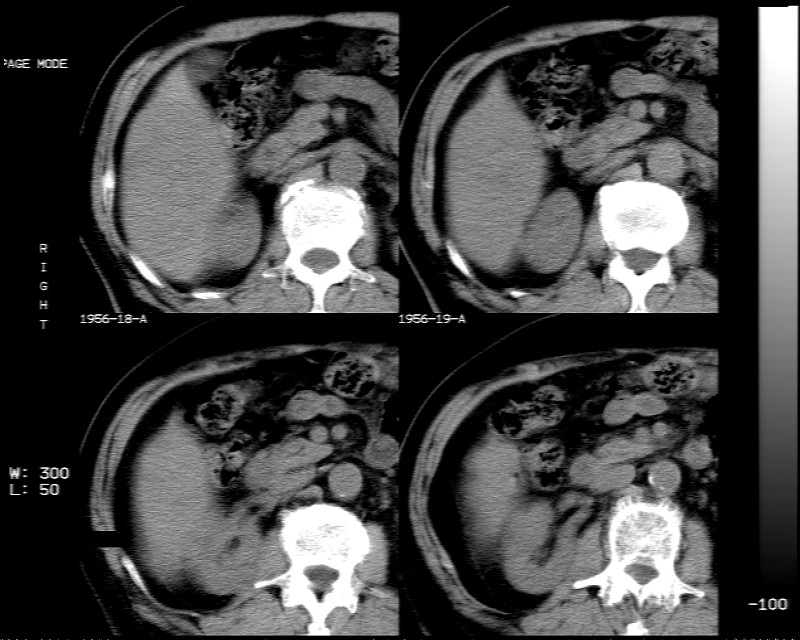

肝脏右叶块状低密度影,增强后动脉期明显强化,门脉期强化减低,延迟期病灶又成低密度。考虑肝细胞癌。我认为比较典型。

低密度肿块,动脉期明显强化,可见星状低强化区,门脉期强化向中心扩展,但病灶动脉期强化最明显,门脉期及平延迟期强化减低,结合病只考虑巨大局灶性结节增生,血管瘤不除外

肝右叶块状低密度影,增强后动脉期病灶明显强化,门脉期及延迟期强化减低。

考虑血管瘤可能性大。

肝右叶巨大占位性病变,平扫呈低密度改变,增强扫描动脉期病灶周围强化,门脉期强化未退出,延时期病灶周边强化与肝实质接近,病灶中心在各期均可见星状不强化区;首先考虑局灶性结节增生可能性大,其次为血管瘤。肝癌不能完全排外(不首先考虑肝癌是因为强化不支持快进快出特点)。

平扫示:肝右后叶下段内见类圆形略低密度占位病灶,边界尚清楚,最大径约为102×71mm,ct值31~41hu。

动态增强扫描示:动脉期病灶显著不均性强化,病灶强化密度高于肝实质;平衡期病灶呈等密度;延迟扫描病灶密度略低于肝实质;三期均见占位病灶内有裂隙状无强化影。肝内胆管无扩张,腹膜后未见肿大淋巴结。

拟诊:肝右后叶下段内占位性病变,考虑为肝结节样增生。

建议进一步检查(mri/或穿刺活检),不排外肝ca。